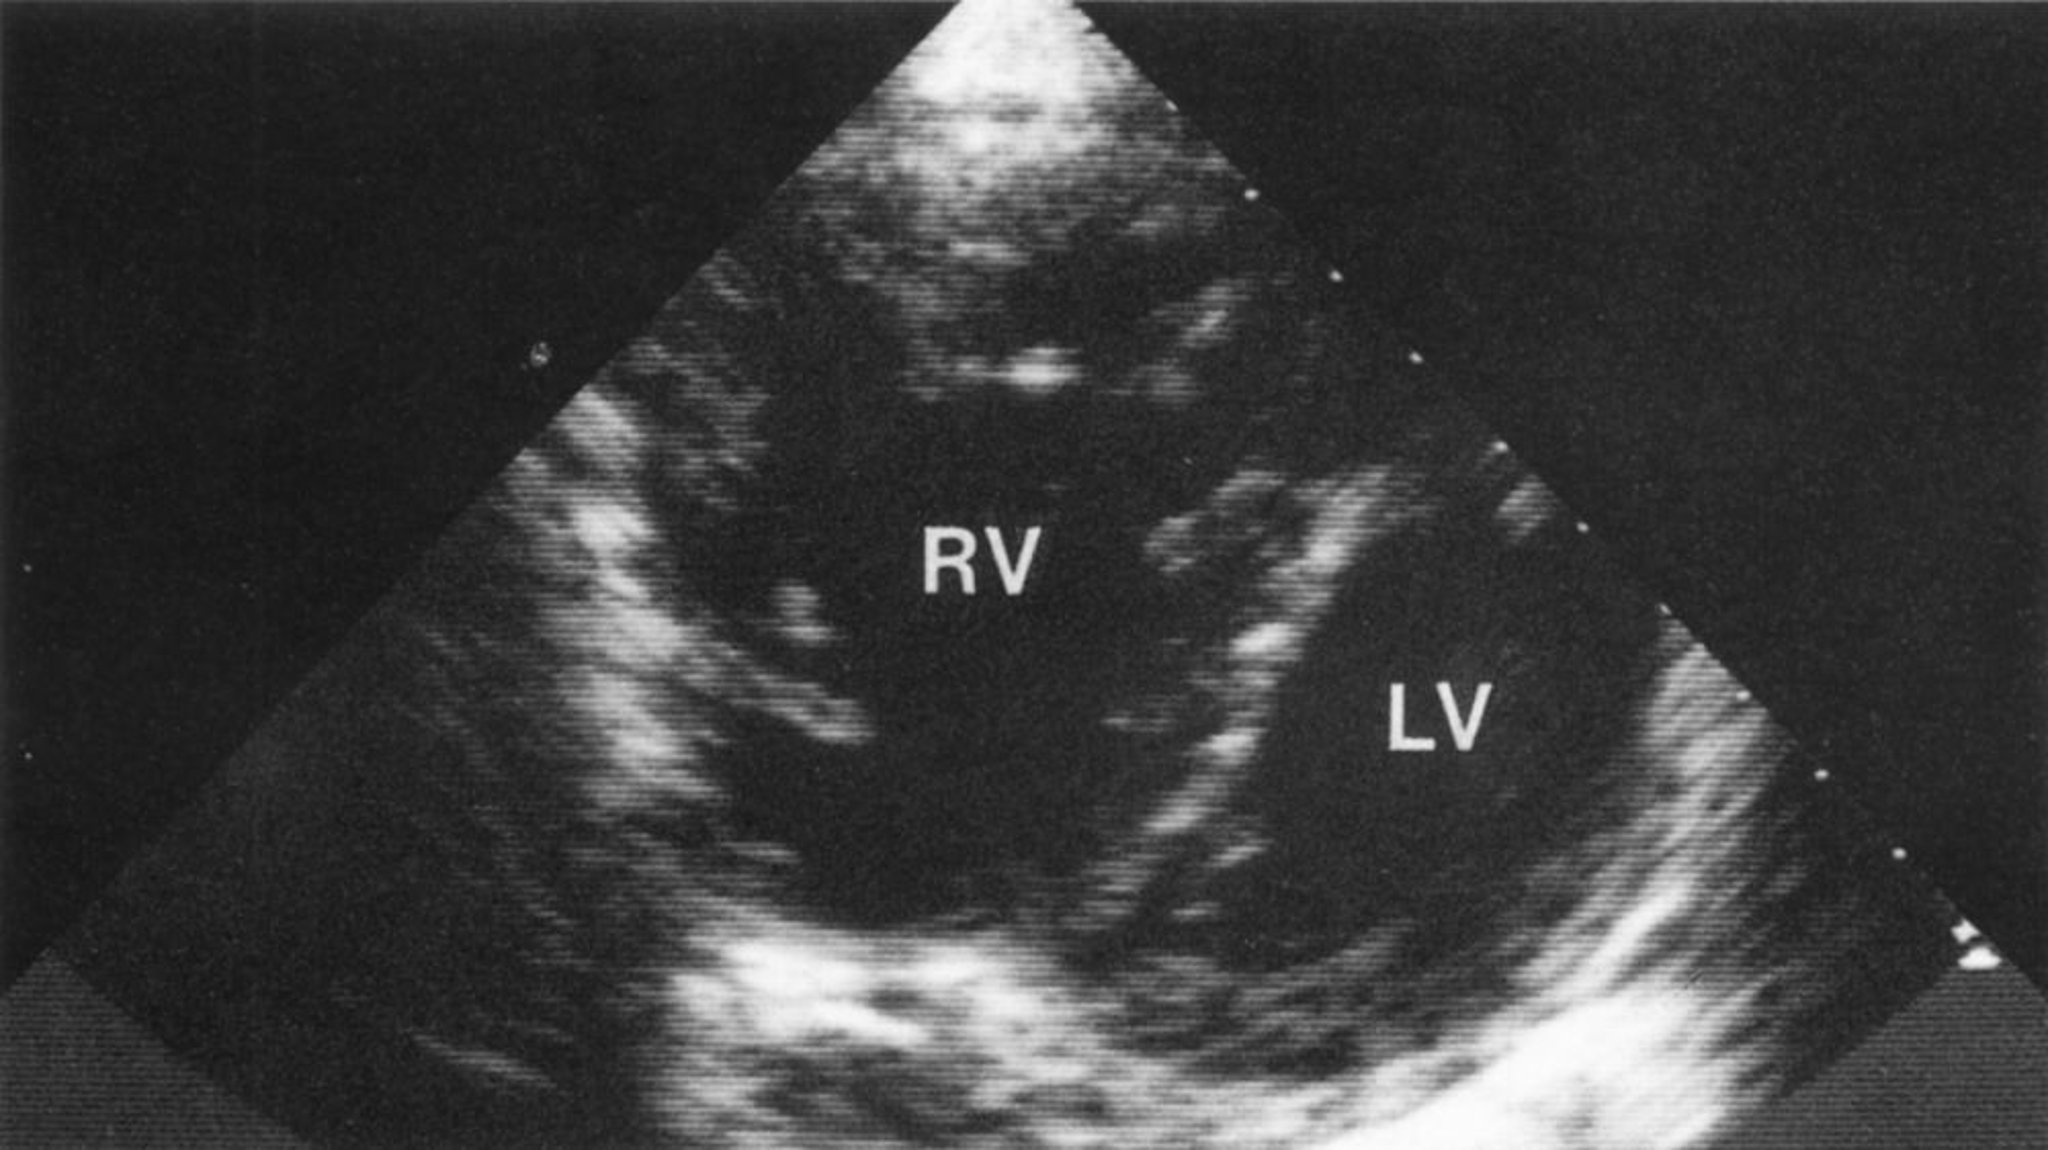

左室および右室機能を評価するため,心エコー検査または核医学検査を施行する;心エコー検査では右室の収縮期圧を評価できるが,肺疾患のために技術的な制約を受けることが多い;一部の患者では心臓MRIが心腔および機能の評価に役立つことがある。確定診断には右心カテーテル検査が必要になることがある。

右室の著明な拡大と右室肥大を示した短軸像。心室中隔が左室側に異常に弯曲していることで,左室の輪郭がD字型になる特徴的所見(D shape)が認められ,これは右室に対する容量および圧負荷と一致する。

© Springer Science+Business Media